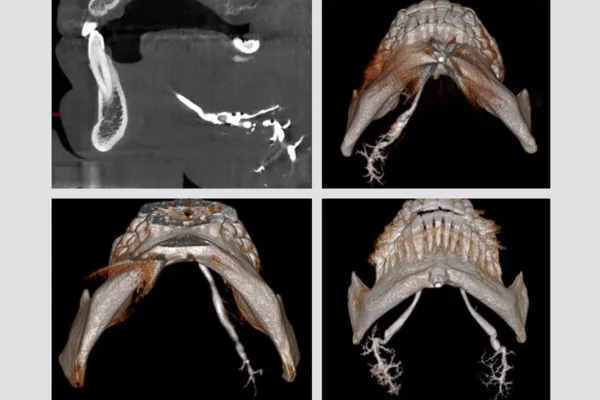

Imagerie par sialographie - 3d cone-beam ct

Auteurs : H. BERTIN, R. BONNET, E. MOURRAIN-LANGLOIS, AS. DELEMAZURE, J. MERCIER, P. CORRE Chirurgie Maxillo-faciale et Stomatologie, CHU de…

Lire la suite →